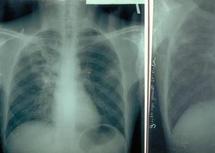

Dans une déclaration à Libé en marge de cette rencontre, le pneumologue et président de la LMCT, Abderraquib Merbouha, a indiqué que 25.562 cas de tuberculose ont été enregistrés au Maroc en 2007, précisant que la cadence du recul de cette maladie est faible au niveau national, sachant que 82 personnes sur 100.000 en sont atteintes.

Rappelant que le bacille de Koch affecte 500 mille personnes par an dans le monde, M. Merbouha a mis l'accent sur les capacités de propagation de la tuberculose en l'absence de traitement des cas déclarés.

Il a appelé la société civile à jouer pleinement son rôle de sensibilisation au dépistage de la tuberculose et souligné l'importance de la formation continue du personnel médical et paramédical dans la lutte contre cette maladie.

Il a également salué les efforts déployés par le ministère de la Santé qui prend en charge le traitement et l'hospitalisation des tuberculeux, estimant cependant qu'il reste beaucoup à faire en matière de lutte contre cette maladie.

Cette rencontre a été ponctuée par la projection d’un film traitant de la tuberculose suivi d’un exposé scientifique en arabe dialectal sur les causes, les symptômes de la tuberculose et les moyens de sa prévention et de son traitement. C’est ainsi que 125 participants ont bénéficié de cette journée de sensibilisation supervisée par M.Merbouha et Karim Kaali, major du CDTMR.

La stratégie marocaine 2006-2015 de lutte antituberculeuse vise à accélérer la cadence du recul de cette maladie, maintenir le niveau de diagnostic, porter le taux de succès de traitement à plus de 90 % et à réduire de 50% le taux de propagation et de mortalité à l'horizon 2015, conformément aux objectifs du Millénaire pour le développement.